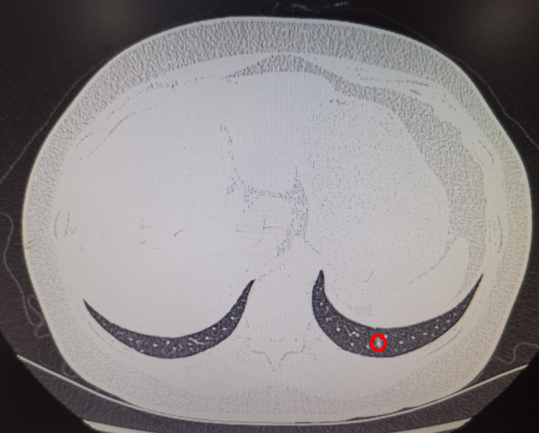

ENB-MWA患者术前小结节位置及消融术后3天复查CT见病灶区域成消融后炎性改变(完全覆盖结节位置)。

2例ENB下肺外周磨玻璃样结节(GGO)术前定位,难度大,尤其是患者肺GGO位于左肺下叶后基底段紧靠膈面,大小约0.6mm,常规CT引导下定位准确性极低。在电磁导航支气管镜引导经肺实质结节通道技术(ENB-TPNA)支持下准确定位,并行微创肺楔形切除术。